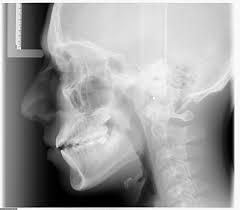

Hisatugu Numata fue el primero en experimentar un método para obtener una radiografía panorámica.

Dr. Yrlo Veli Paatero desarrollo la ortopantografia.